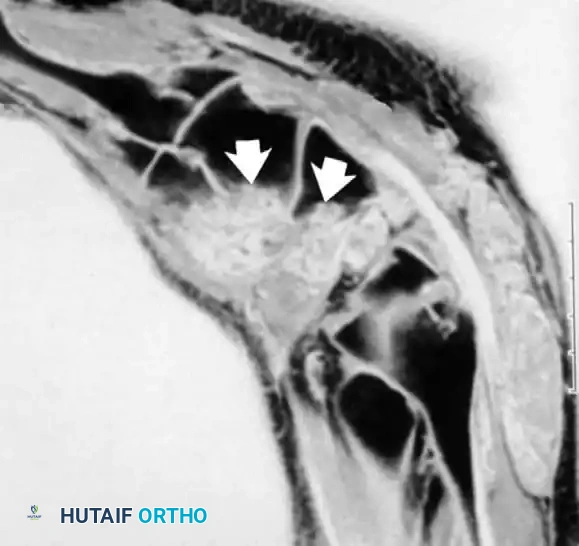

تعتبر حالات مثل مرض كينبوك (تنخر العظم الهلالي) وتنخر العظم الزورقي (الذي يحدث غالباً بعد الكسور) من الحالات التي يبرع الرنين المغناطيسي في تشخيصها مبكراً. يشير فقدان الإشارة الطبيعية لدهون نخاع العظم في صور الرنين إلى نقص التروية الدموية وموت الخلايا العظمية.

تنخر العظم الهلالي في المعصم أو ما يعرف بمرض كينبوك كما يظهر في الرنين المغناطيسي

تنخر العظم الزورقي بعد التعرض لكسر في اليد